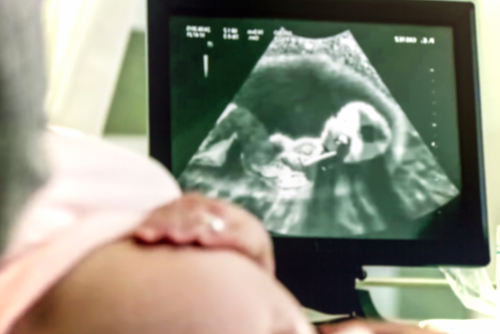

The Union Health Ministry on Friday said checkups under the Pradhan Mantri Surakshit Matritva Abhiyan (PMSMA) launched in 2016 for quality pregnancy checkups on the ninth of every month have reached the one crore-mark.

"In order to enable early detection of high risk pregnancies, 84 lakh haemoglobin tests, 55 lakh HIV tests, 41 lakh tests for gestational diabetes, 33 lakh tests for syphilis and more than 15 lakh ultrasounds have been conducted under the programme based on the individual requirements of pregnant women," said Nadda. He said based on the clinical conditions and investigations, over 5.50 lakh pregnant women were identified with high risk pregnancies and referred to a specialist or a higher health facility for appropriate care.